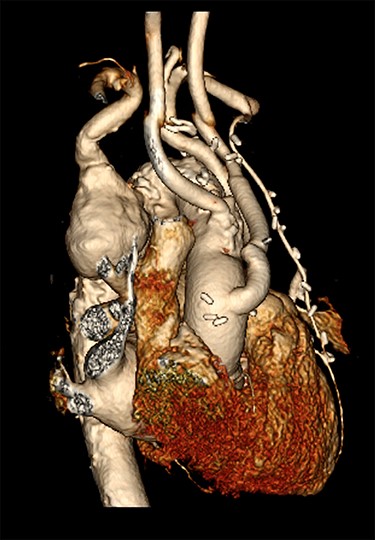

CT reconstruction illustrating a debranched left common carotid artery and subclavian artery with double coronary artery bypass graft (left internal mammary artery to left anterior descending, and saphenous vein T graft to obtuse marginal artery).

The initial procedure, performed via a median sternotomy, involved debranching the left common carotid artery (CCA) and left SCA with simultaneous double vessel CABG (left internal mammary artery to left anterior descending, and saphenous vein T graft to obtuse marginal artery) (Fig. 2). This provided a sufficient landing zone for a thoracic aortic stent graft. His post-operative recovery was complicated by atrial fibrillation, hospital acquired pneumonia and delirium requiring reintubation for severe agitation. The patient was discharged home following rehabilitation with a plan to perform the second stage of the repair as a semi-elective procedure.